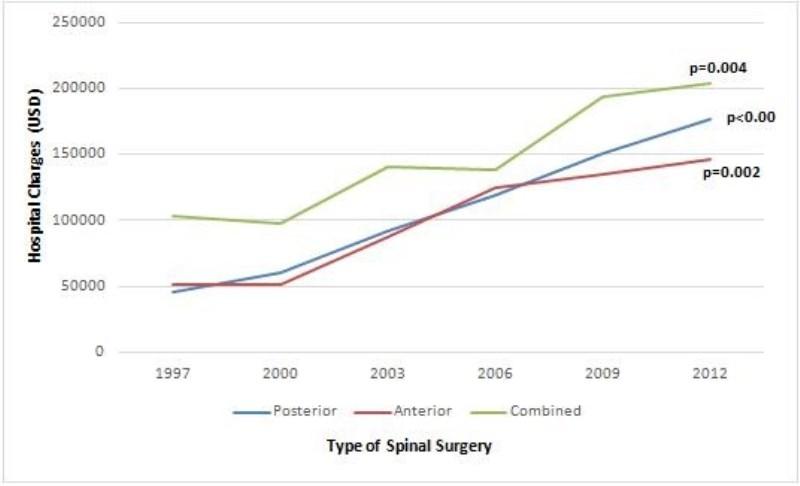

总平均住院费用(成本通胀调整为2012年)是119613美元(表 2),在成本通胀调整为2012年时(图 2),所有类型手术的平均住院费用均有所增加。对于后路手术,1997年的平均成本为45947美元,2012年的176791美元(P<0.001)。对于前路手术,费用增加2.8倍,(P<0.002);而对于前后路联合手术,费用增加了1.98倍,(P<0.004)。

图2 15年研究期内不同术式住院费用趋势

15年的研究数据显示EOIS 患者后路手术显著增加,但总体手术率明显下降;患儿住院费用显著增加,后路对于前路手术,费用增加2.8 倍,而对于前后路联合手术,费用增加了1.98 倍。研究结果为进一步开展EOS的治疗,特别是制定降低成本策略提供参考。